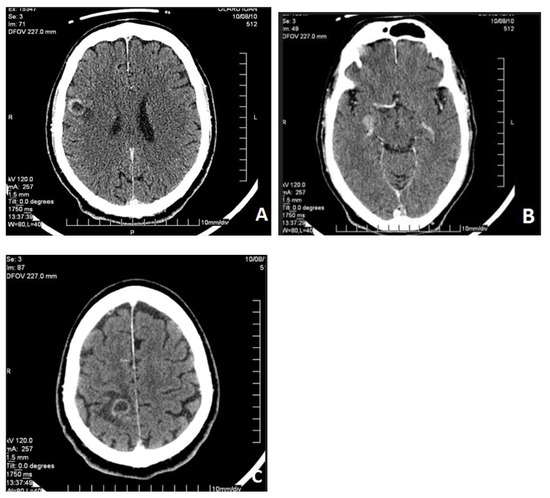

Metastatic melanoma is one of the most common malignancies associated with the spread of the primary tumor. The primary site is usually the skin or the eyes. The most frequent site of metastases is the gastrointestinal tract, accounting for 60% of cases at [...] Read more.

Metastatic melanoma is one of the most common malignancies associated with the spread of the primary tumor. The primary site is usually the skin or the eyes. The most frequent site of metastases is the gastrointestinal tract, accounting for 60% of cases at autopsy. In 2% of patients, metastases occur without a detectable primary tumor. We present a rare case of upper digestive bleeding caused by multiple gastrointestinal tract metastases from an amelanotic melanoma. This case report describes a 65-year-old male who arrived at the emergency department after experiencing an episode of upper gastrointestinal bleeding (melena). One week prior to admission, he had been treated with nonsteroidal anti-inflammatory drugs for lower back pain due to L4–L5 disc herniation. Upper digestive endoscopy revealed multiple polypoid masses in the stomach and duodenum, and capsule endoscopy showed additional lesions in the small bowel. Histopathological examination confirmed the diagnosis: metastases from an amelanotic malignant melanoma. Abdominal and cranial computed tomography scans revealed multiple secondary lesions in the brain, gallbladder, retroperitoneal area, gastrointestinal tract, and peritoneum. Localized radiotherapy was applied to the cerebral metastasis, and systemic chemotherapy with dacarbazine was initiated, resulting in a partial clinical response. Unfortunately, the disease progressed, and the patient died one month after diagnosis. Metastatic melanoma of the gastrointestinal tract is an exceedingly rare cause of upper digestive bleeding. Full article